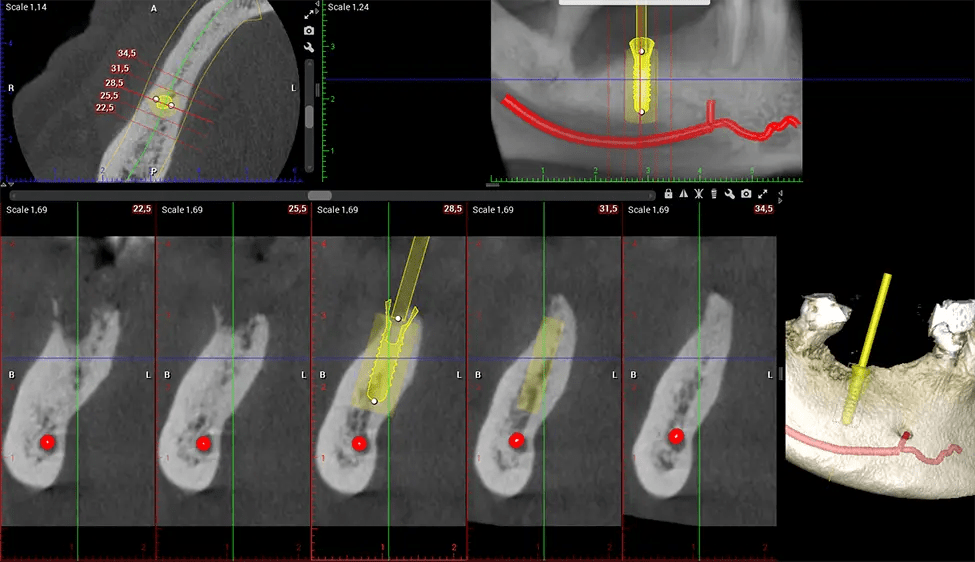

Another significant benefit is that 3D imaging provides more precise images of your bone structure. These images are more detailed, providing you with a more accurate diagnosis. An accurate diagnosis means better treatment for you.

When paired with extractions, dental implant placement, or bone grafting, CBCT technology can provide you with a quicker and much more comfortable experience. This is because the 3D image provides a more detailed picture of your entire oral cavity, allowing your dentist to walk you through each step of the process before it occurs. This often helps patients feel more prepared and comfortable overall, especially if they have had a traumatic experience with past dental treatments.

Planmeca Viso G7 CBCT ( Cone Beam CT Scan ) is designed to surpass the demands of industry leaders, specialists, and large institutions. It’s has a large ø25×30 cm sensor with four built-in cameras. It can capture unlimited volume sizes from a ø3×3 cm to a ø30x30cm volume capturing the skullcap through C7 on the cervical spine. The Planmeca Viso G7 offers the industry’s largest single volume scan of ø30×19 cm. It’s poised to handle advanced imaging modalities such as Planmeca ProFace® and Planmeca 4D™ Jaw Motion technology. The occipital head support allows an unimpeded view of facial tissue.

Our patented SCARA technology enables doctors to capture True Extraoral Bitewings that are as accurate at detecting caries as a 2D bitewing series, but with half the radiation dose. With our bitewings, doctors can view the apices of teeth on both jaws providing a more comprehensive view of the patients’ anatomy.